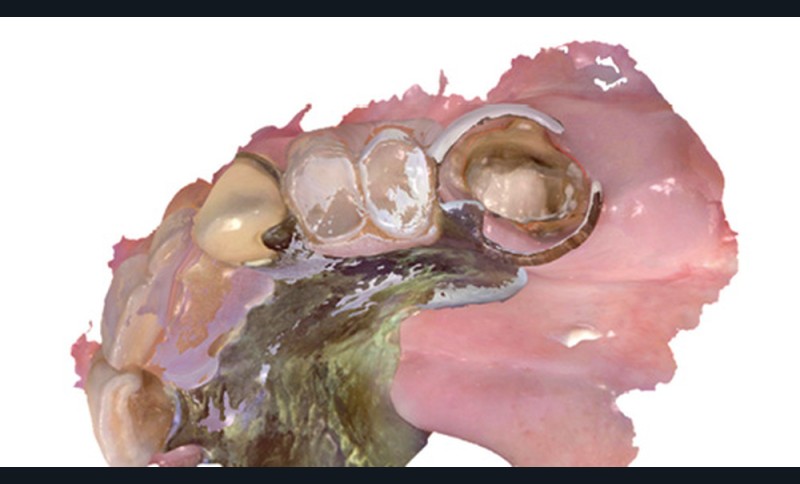

La corrélation de fichiers est un vrai facilitateur pour les plans de traitement prothétique ; que ce soit pour le suivi des cas, ou dans des cas particuliers comme celui de la couronne sous châssis. Cette situation est toujours préjudiciable pour le patient en empreinte conventionnelle, car elle oblige à priver ce dernier de sa prothèse adjointe le temps que le laboratoire conçoive la couronne. Avec l’empreinte optique, il suffit d’enregistrer le crochet et sa position par rapport à la préparation pour que le prothésiste puisse concevoir une prothèse adaptée à la cavité buccale et à la prothèse amovible. Autre cas particulier, lors de la réalisation d’inlay-core, les logiciels de laboratoire ont des algorithmes qui autorisent la conception en seul temps de l’inlay-core et de la couronne avec un calcul des morphologies des éléments pour qu’ils respectent à la fois l’homothétie et les épaisseurs minimales de matériau (fig. 3 et 4).